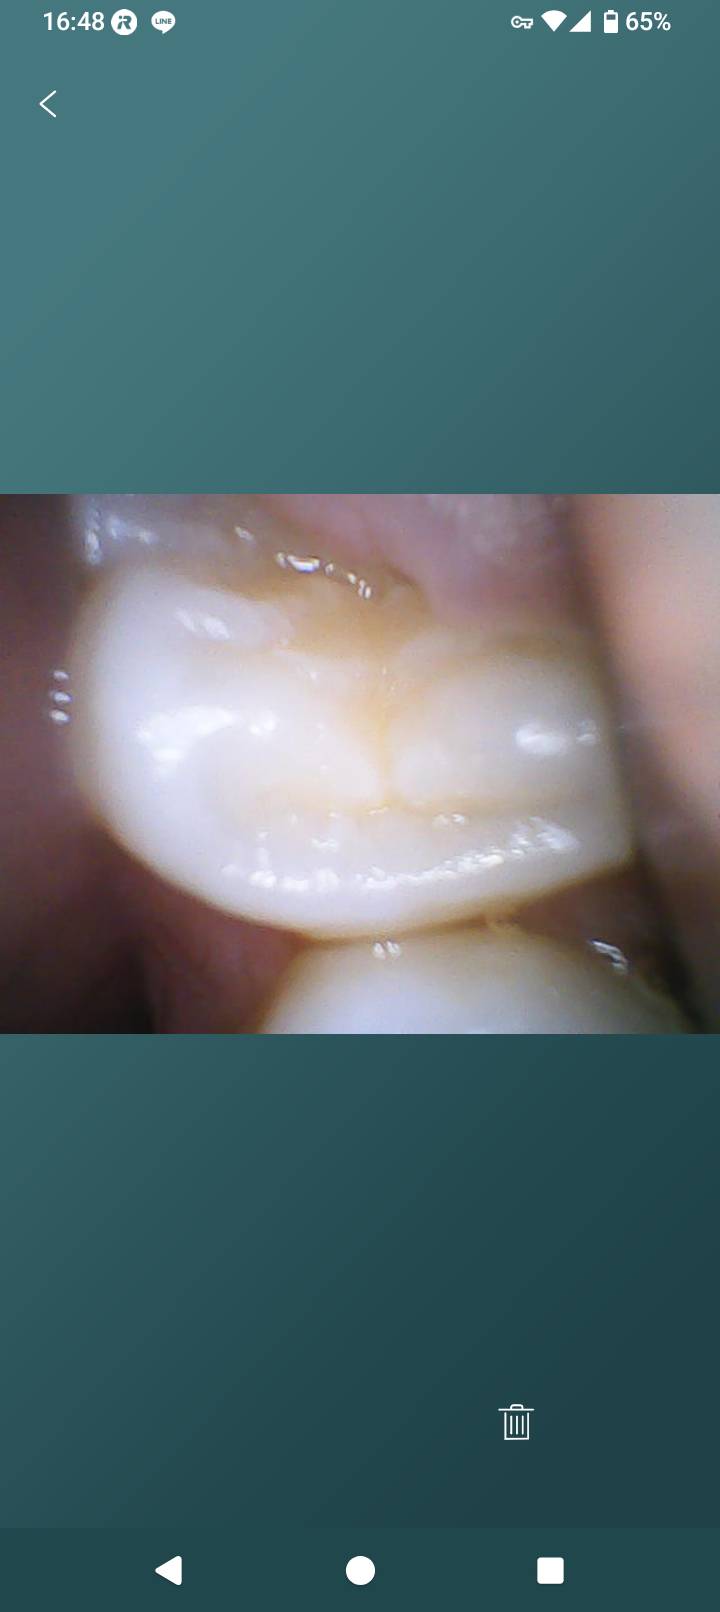

12歳になりたての息子の12歳臼歯が1月頃から下左右2本生えはじめました。

歯肉弁が半分残っている状態からひと月くらい変化がありません。

画像1

折角写真を上げて頂いたのですが、鮮明でないため判断材料になりませんでした。

歯肉弁があると歯垢が溜まりやすくむし歯になりやすいと思います。

一つの考え方として「一回切除してみる」はありだと思います